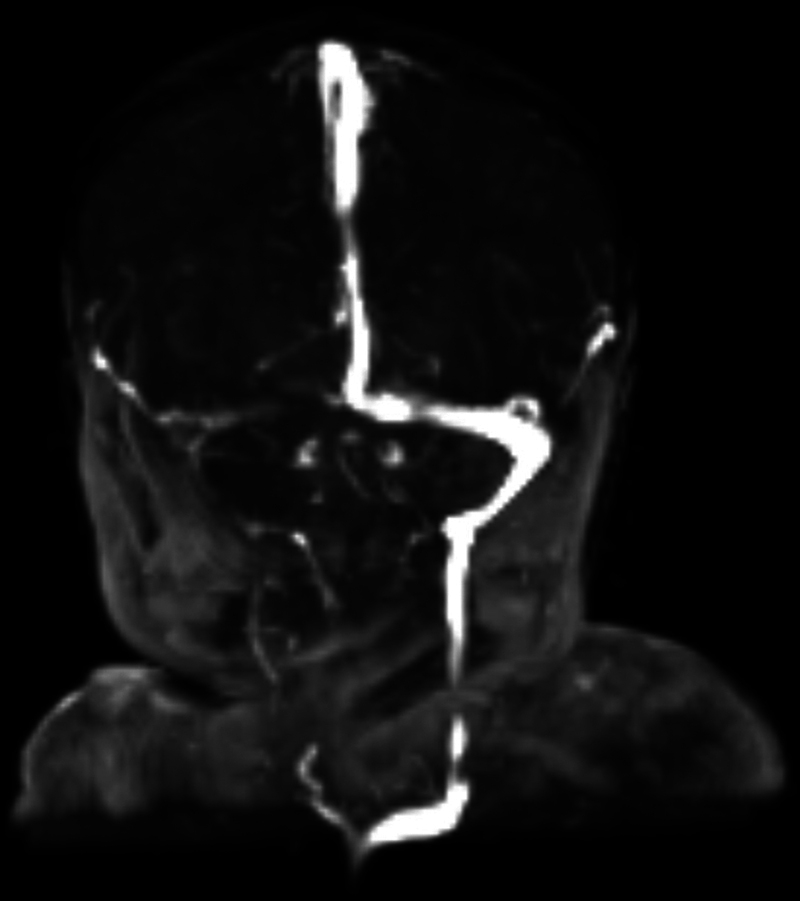

Background  Gestational alloimmune liver disease (GALD) is characterized by maternal IgG-directed fetal hepatocyte damage and can lead to severe liver failure and fetal or infant death. Moreover, GALD is associated with a near 90% risk of recurrence in subsequent pregnancies. Case  We present a case of a newborn patient delivered to a 32-year-old G2P1000 mother who received prolonged antenatal intravenous immunoglobulin (IVIG) treatment during the current pregnancy due to the neonatal death of the first child from GALD-related liver failure. Postnatal testing, including a liver magnetic resonance imaging (MRI) and buccal biopsy of this newborn, showed normal morphology of the liver without any abnormal iron deposition. Additional laboratory testing showed a lack of any liver injury. Conclusion  This case supports the use of antenatal IVIG immunotherapy to prevent the recurrence of GALD in subsequent pregnancies. Key Points GALD can lead to severe fetal liver injury.GALD is highly recurrent in subsequent pregnancies.Prophylactic IVIG may prevent GALD recurrence.

Abstract Image